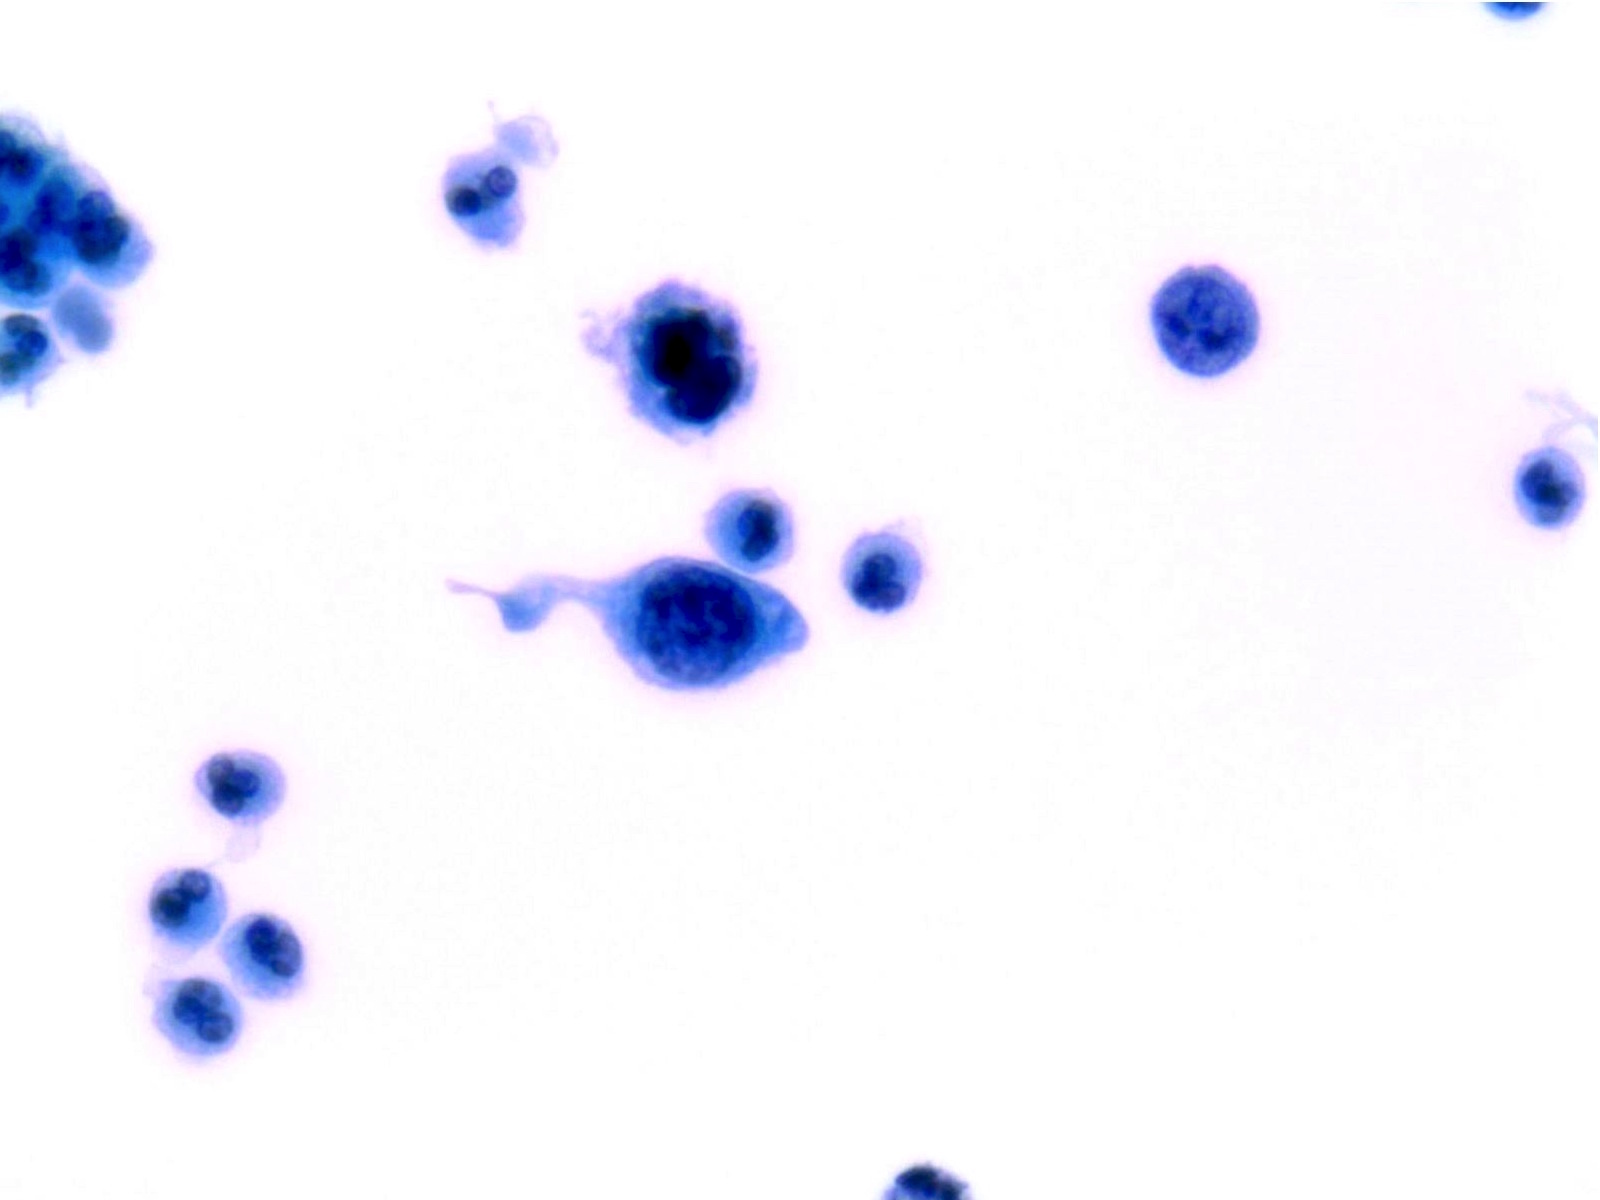

High Grade Urothelial Carcinoma (HGUC)

-

Notes:

- Urine cytology cannot distinguish invasive HGUC and carcinoma in Situ (CIS)

- Squamous or glandular differentiation of urothelial carcinoma may be seen in urine cytology but a diagnosis of squamous cell carcinoma or adenocarcinoma of the urinary tract can only be made after examination of biopsy or cystectomy specimens

- HGUC is diagnosed on the basis of this criteria according to the Paris System consensus:

- Cellularity; at least 5 - 10 abnormal cells

- N:C ratio: 0.7 or greater

- Nucleus: moderate to severe hyperchromasia

- Nuclear membrane: markedly irregular

- Chromatin: coarse / clumped

- Other notable cytomorphologic features of HGUC are

- Cellular pleomorphism

- Marked variation in cellular size and shapes. i.e., oval, rounded, elongated or plasmacytoid (comet cells)

- Scant, pale or dense cytoplasm

- Prominent nucleoli

- Mitoses

- Necrotic debris

- Inflammation